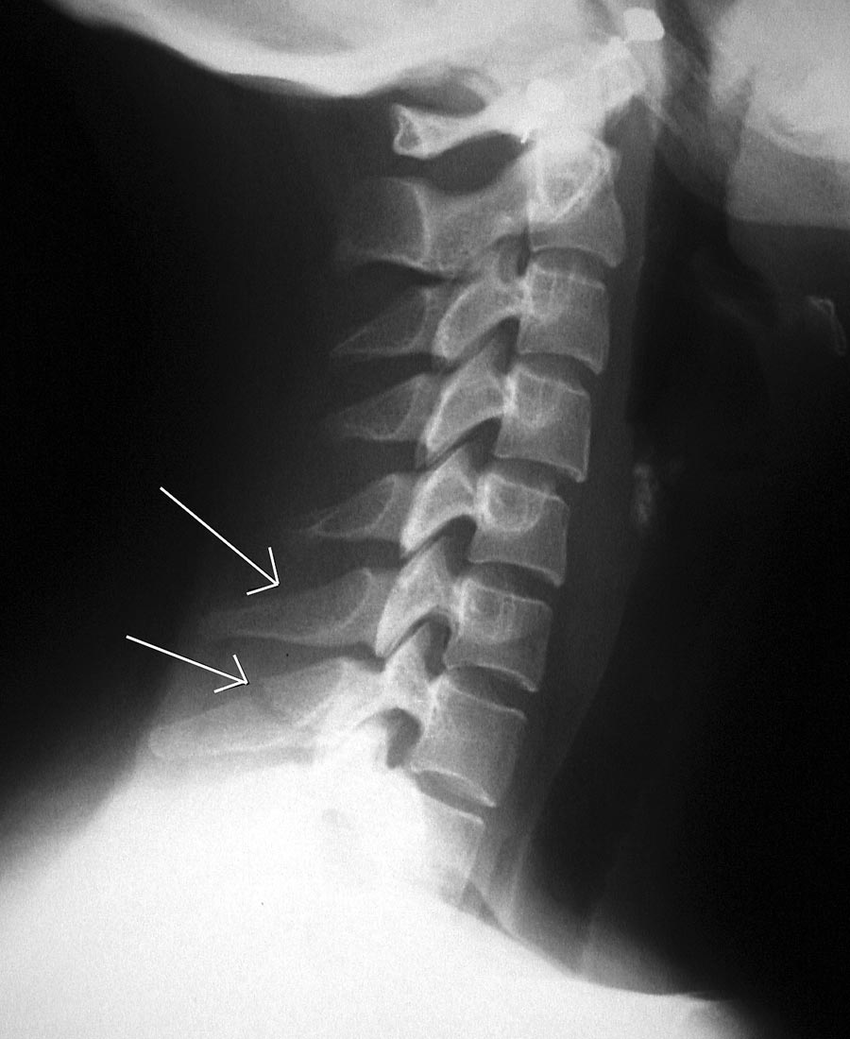

Clay shoveler kırığı

- Alt boyun ve üst göğüs omurgalarının dikensi uzantılarında oluşan kırığa denir.

Kaynak: https://www.researchgate.net/profile/Tim_Hunter5/publication/8452212/figure/fig8/AS:364948363464705@1464021878249/Clay-shoveler-fracture-Lateral-view-of-the-cervical-spine-shows-fractures-of-the-spinous.png